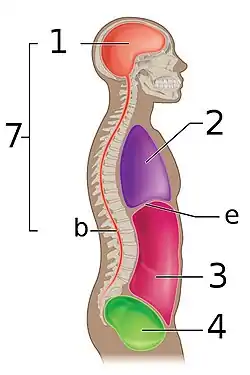

The various cavities of the human body as seen in a lateral projection, with the pelvic cavity labeled 4. | |

The pelvic cavity is a body cavity that is bounded by the bones of the pelvis. Its oblique roof is the pelvic inlet (the superior opening of the pelvis). Its lower boundary is the pelvic floor.

The pelvic cavity primarily contains the reproductive organs, urinary bladder, distal ureters, proximal urethra, terminal sigmoid colon, rectum, and anal canal. In females, the uterus, fallopian tubes, ovaries and upper vagina occupy the area between the other viscera.[1][2]

The rectum is located at the back of the pelvis, in the curve of the sacrum and coccyx; the bladder is in front, behind the pubic symphysis. The pelvic cavity also contains major arteries, veins, muscles, and nerves. These structures coexist in a crowded space, and disorders of one pelvic component may impact upon another; for example, constipation may overload the rectum and compress the urinary bladder, or childbirth might damage the pudendal nerves and later lead to anal weakness.